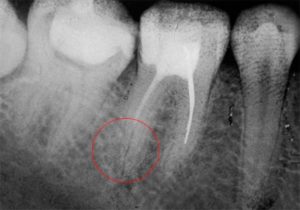

- Еще одна причина делать рентгеновский снимок после пломбирования — определение границ установленной пломбы. Если у вас болит зуб после пломбирования каналов, вполне возможно, что внутри осталось незапломбированное пространство или часть композита выходит за пределы зуба со стороны челюсти.

После пломбирования каналов материал оказался за пределами корня

Неправильный размер пломбы

Если зубная боль появляется после или во время приема пищи, значит, пломбирование зуба было проведено с нарушениями. Стоматолог мог поставить неподходящую по размеру пломбу на жевательные зубы. Причем она может быть:

- слишком маленькой – внутри осталось незапломбированное пространство, которое можно увидеть только на рентген-снимке;

- ошибки в пломбировании канала (неплотное заполнение канала композитом, выход цемента за контур зуба, перфорация канала или корня, инородное тело в полости зуба и т.д.),

11. Киста или гранулема корня

Эти два заболевания чаще возникают как осложнения пульпита, когда нервная ткань разрушается, и продукты гниения попадают в корень зуба. Тогда в лунке, где он крепится, начинается воспалительный процесс, причиняющий сильную боль. В зависимости от локализации воспаления и его интенсивности с помощью рентгенографии диагностируется либо гранулема, либо киста верхушки корня.

Помимо перфорации стоматолог может допустить и другие ошибки. Частой ошибкой является выведение пломбировочного материала за изначальную форму зуба. Подобное особенно неприятно при глубоком пломбировании каналов корней зуба. Может возникнуть боль при накусывании, образоваться отечность и гиперемия.